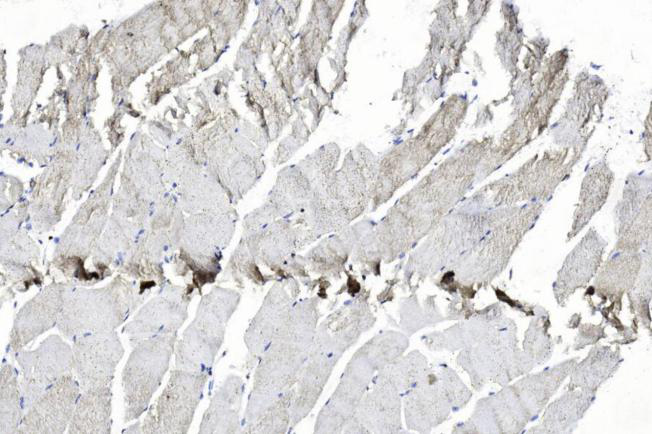

Applikationen WB, FC, IHC-P

IHC: 1:400

IHC-P: 1:200